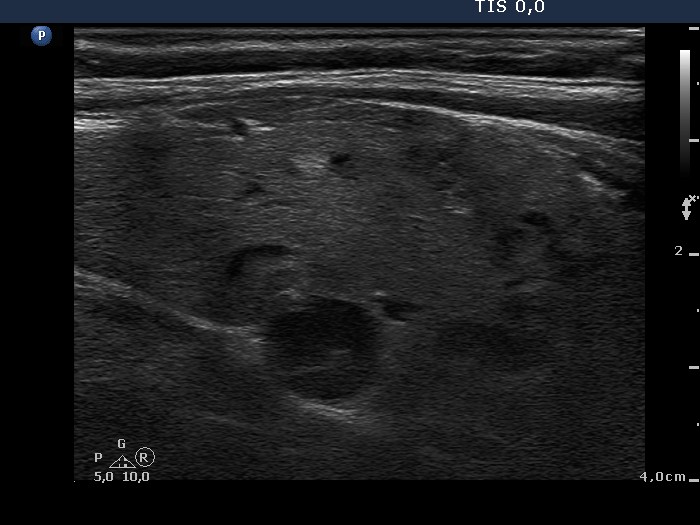

Ultrasonography. The thyroid was composed of multiple nodules with different echogenicities. There was a small hypoechogenic lesion above the right lobe.